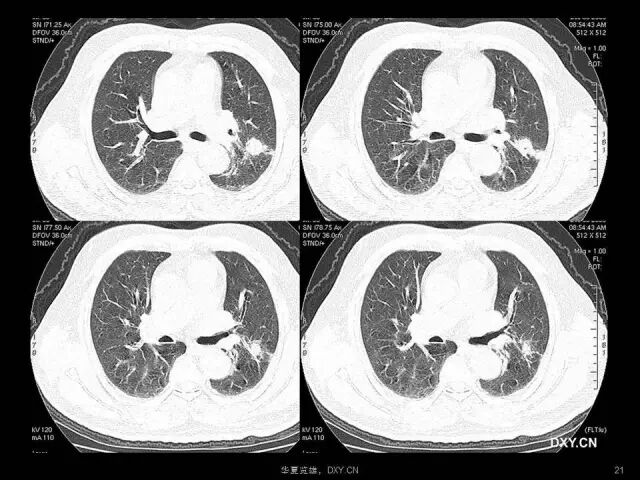

肺炎、肺癌、肺结核在影像学上的征象往往千变万化。